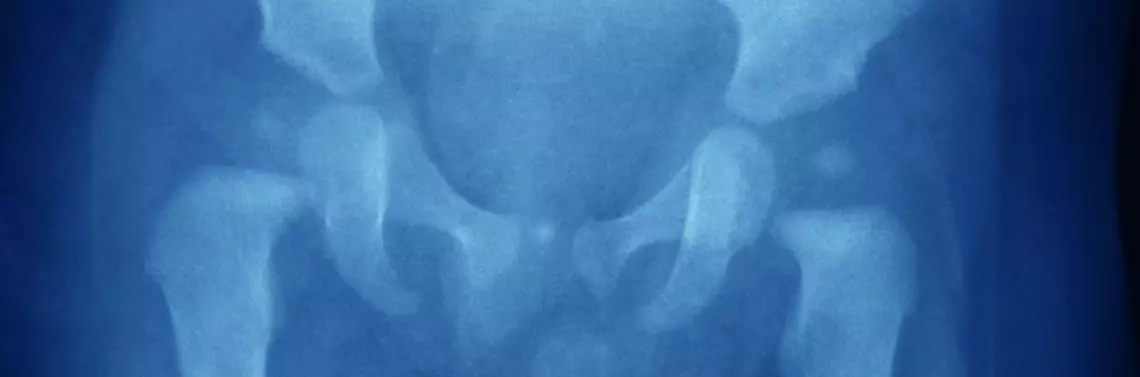

Dysplazja stawów biodrowych (dysplasia coxae congenita) rozumiana jest jako choroba uwarunkowana genetycznie o nie do końca wyjaśnionej etiologii, związana z niedorozwojem panewki stawowej (zbyt płytka panewka), a także słaby rozwój pozostałych struktur okołostawowych. W miarę upływu czasu na skutek wzmacniania się miękkich elementów stawu i wzmożenie napięcia w jego obrębie dochodzi do wysunięcia głowy kości udowej z panewki. Taki obrót sprawy predysponuje do zwichnięcia stawu biodrowego i problemu w lokomocji dziecka, a także wpływa na jego późniejszy rozwój.

Dysplazja stawu biodrowego